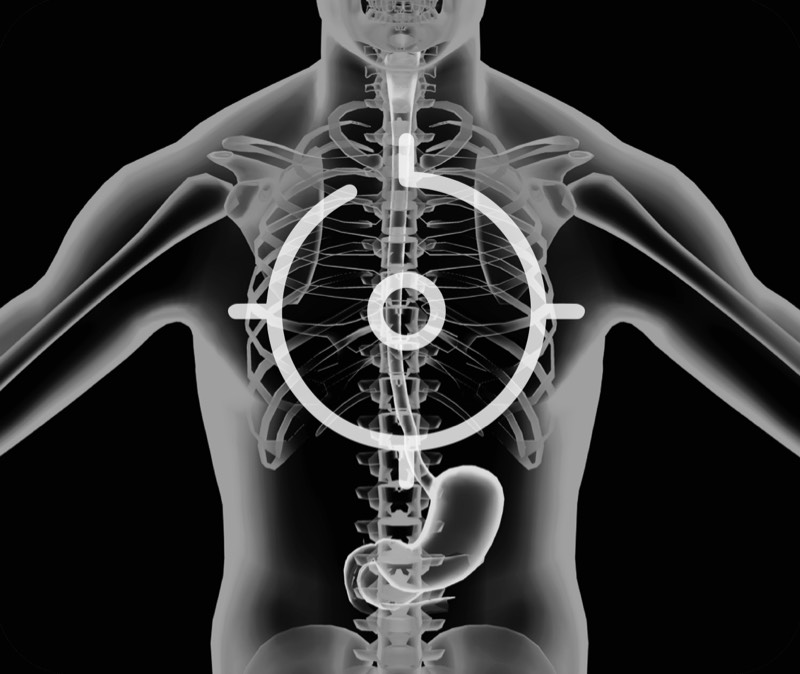

食管内间质瘤清晰显像

卓越的宽频设计,满足医生探查不同深度的组织和器官